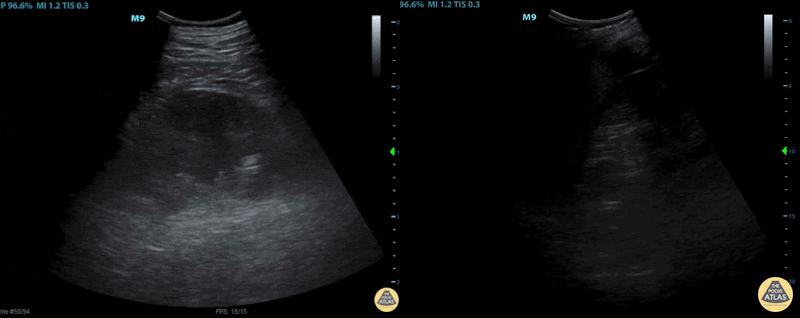

This image demonstrates a subcapsular hematoma of the left kidney (left image) with intraperitoneal hemorrhage (right image). Image courtesy of Cody McIlvain, MD. Resident, Emergency Medicine; Denver Health Residency in Emergency Medicine, Denver, Colorado.